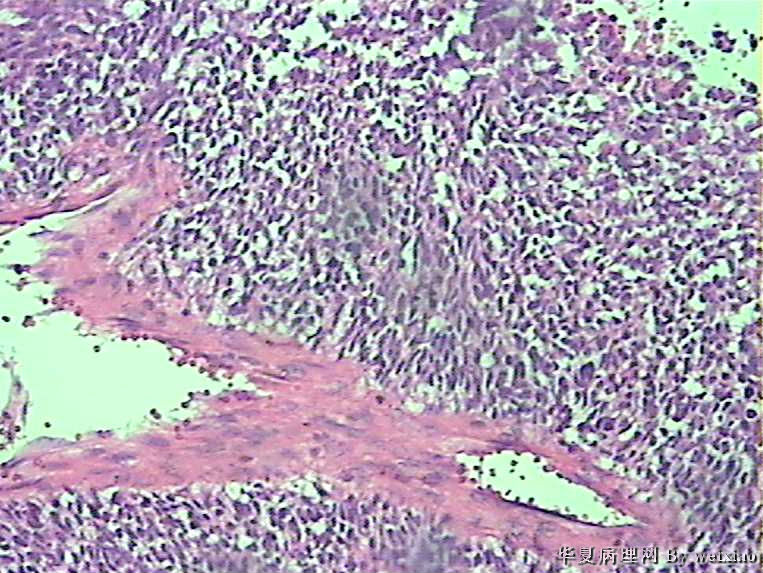

病史:男45岁,头痛2个月,手术所见:额叶占位性病变,与周围正常脑组  织的界限不清。

大体:灰白色碎组织一堆,质软,大小:2.5*1.8*1.3cm

胶质母细胞瘤

坏死+细胞密度+异性+围绕血管现象。

The tumor cells are kind of spindle, need to rule out gliosarcoma, you need to check MRI films, do immunostain for GFAP, and vimentin. The vascular proliferation (VP) supports GBM.

肿瘤细胞呈梭形,血管增生明显,有坏死,符合胶质母。